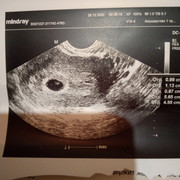

ЗюЗя 83 писал(а):Упс, чуть не забыла док-во прикрепить)))

ЗюЗя 83 писал(а):Вот и сходила я на УЗИ))) нам 5 неделек. Сказала врач,что хорошо развивающаяся беременность. Но есть ретрохориальная гиматома. Но типа ничего страшного. Пришла, почитала в инете что и с чем это едят и как то не по себе. Кому верить? Пишут, что это угроза выкидыша((( страшно.

По месячным 6 недель, а по УЗИ 5 поставили. Сердечко пока ещё не услышали,Записалась 7 на повторное. Спасибо огромное за поздравление)))